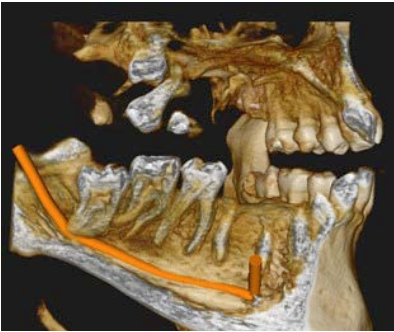

A CBCT scan was acquired using the Carestream CS 8200 to determine the exact 3D relationship between the impacted roots and the IAN canals. The difference between the panoramic view and the CBCT was immediate and clinically decisive.

Cross-sectional views of both sides showed the precise spatial relationship that the panoramic could only hint at. On the right side (LR8), the CBCT confirmed direct contact between the root and the nerve canal. On the left (LL8), the tooth was in close proximity but not in direct contact — a distinction that significantly affects the surgical approach and the informed consent conversation.

But the most powerful output was the 3D volume rendering. The CS 8200's software generated fully rotatable 3D views of both impacted teeth and their nerve canals, showing the anatomical relationship from any angle. These images did not just help the clinician plan — they transformed the patient conversation.

3D volume-rendered view showing the complex relationship between tooth 38 and the mandibular nerve canal 3D volume-rendered view showing the complex relationship between tooth 48 and the mandibular nerve canal

Fig. 4 & 5 3D volume-rendered views showing the complex anatomical relationship between the impacted wisdom teeth and their respective IAN canals. These views were used directly in the patient consultation to explain the surgical risks and secure informed consent.